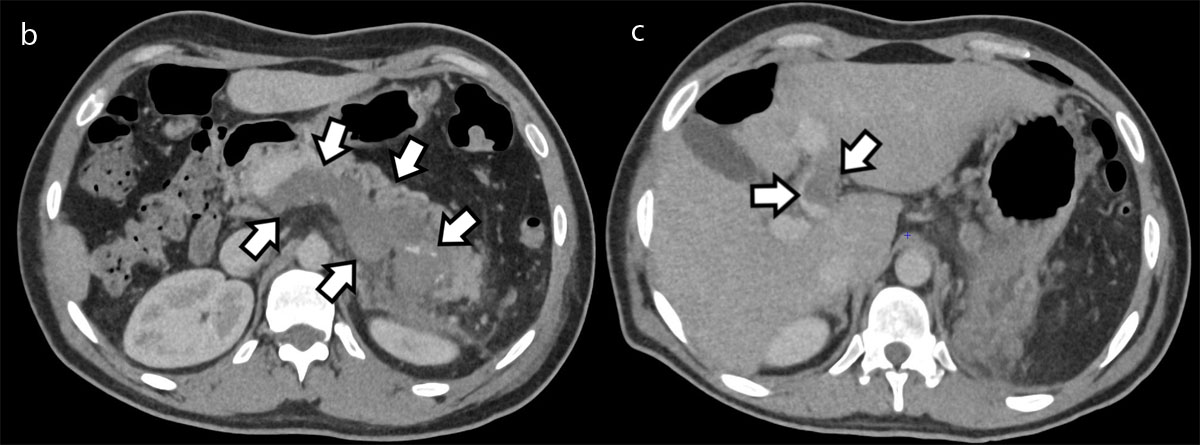

Figure 1b and c

Axial contrast-enhanced portal phase CT slices at the level of the splenic vein (Figure 1b) and portal vein (Figure c) confirming a thrombosis of the splenic vein, extending into the portal vein as well as the part of the intrahepatic segment of the left branch of the portal vein (arrows).